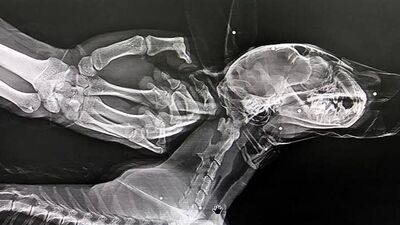

Vücudunda saçmaların isabet ettiği belirlenen yaralı vaşak ameliyata alındı.Vaşağın, Rehabilitasyon Merkezindeki muayenesinde çekilen röntgenlerde vücudunun çeşitli yerlerinde saçma taneleri bulunduğu tespit edildi. Gerekli tedavi ve rehabilitasyon işlemlerinin tamamlanmasının ardından vaşak, doğal ortamına bırakılacak.